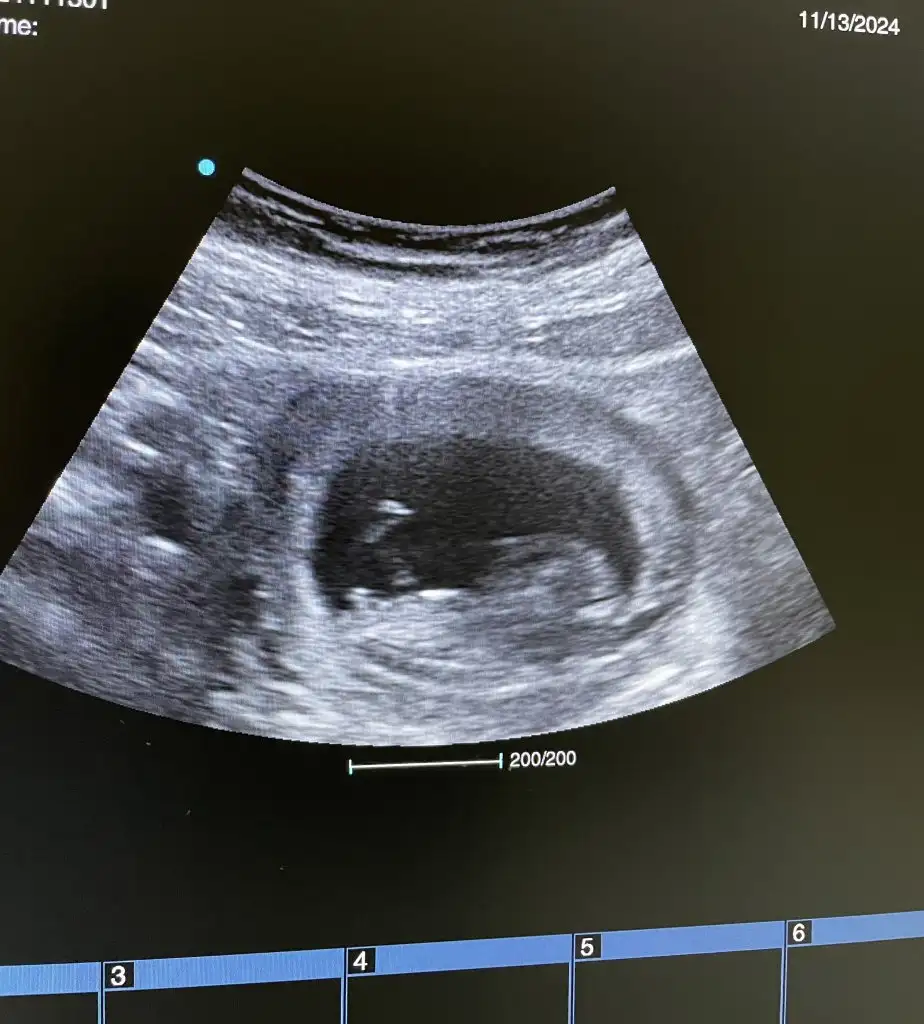

Bugun gittim %90 kiz dedi

Amin insallah saglikli olsunlardaHayırlı evlat olsun insallah Darısı başıma inşallah 2 oglandan sonra bakalım kismetimizde hangisi varsa Rabbim hayırlı evlat eylesin

ay sizinkiyle benim bebiş benziyodu içime bi umut düştüBugun gittim %90 kiz dedi

Bana da tahmin de bulunurmusunuzKız cnm

Bana da tahmin de bulunurmusunuzo zaman Allahım gönlünüze göre versin ama inşallah sağlıklı sıhhatli bir kızçe geliyordur